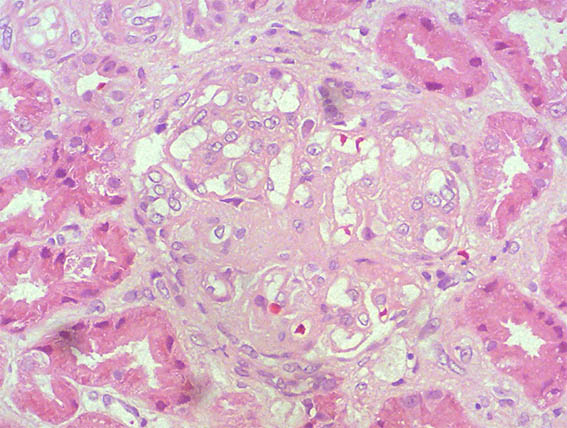

Figure 2. H&E, X400.